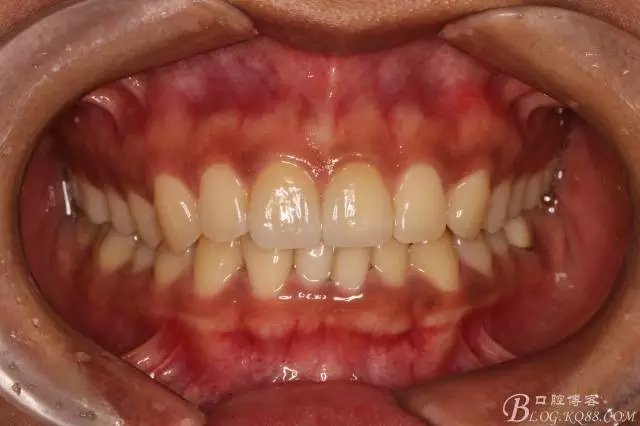

粘接完成即刻照

即刻照局部放大

兩周后復(fù)查(訴11遇冷有點(diǎn)不適,因11備牙有點(diǎn)多,露牙本質(zhì)。囑注意不要進(jìn)食過(guò)冷過(guò)熱食物。癥狀約一個(gè)月后逐漸消失。)

本來(lái)想拍個(gè)微笑像,可惜抓拍幾張都不自然,就留了這張。(兩周復(fù)查時(shí))

半年后(2016.9)復(fù)查照(這次復(fù)查已完全適應(yīng)修復(fù)后的效果,冷熱也不敏感了,我的心也就放下了)